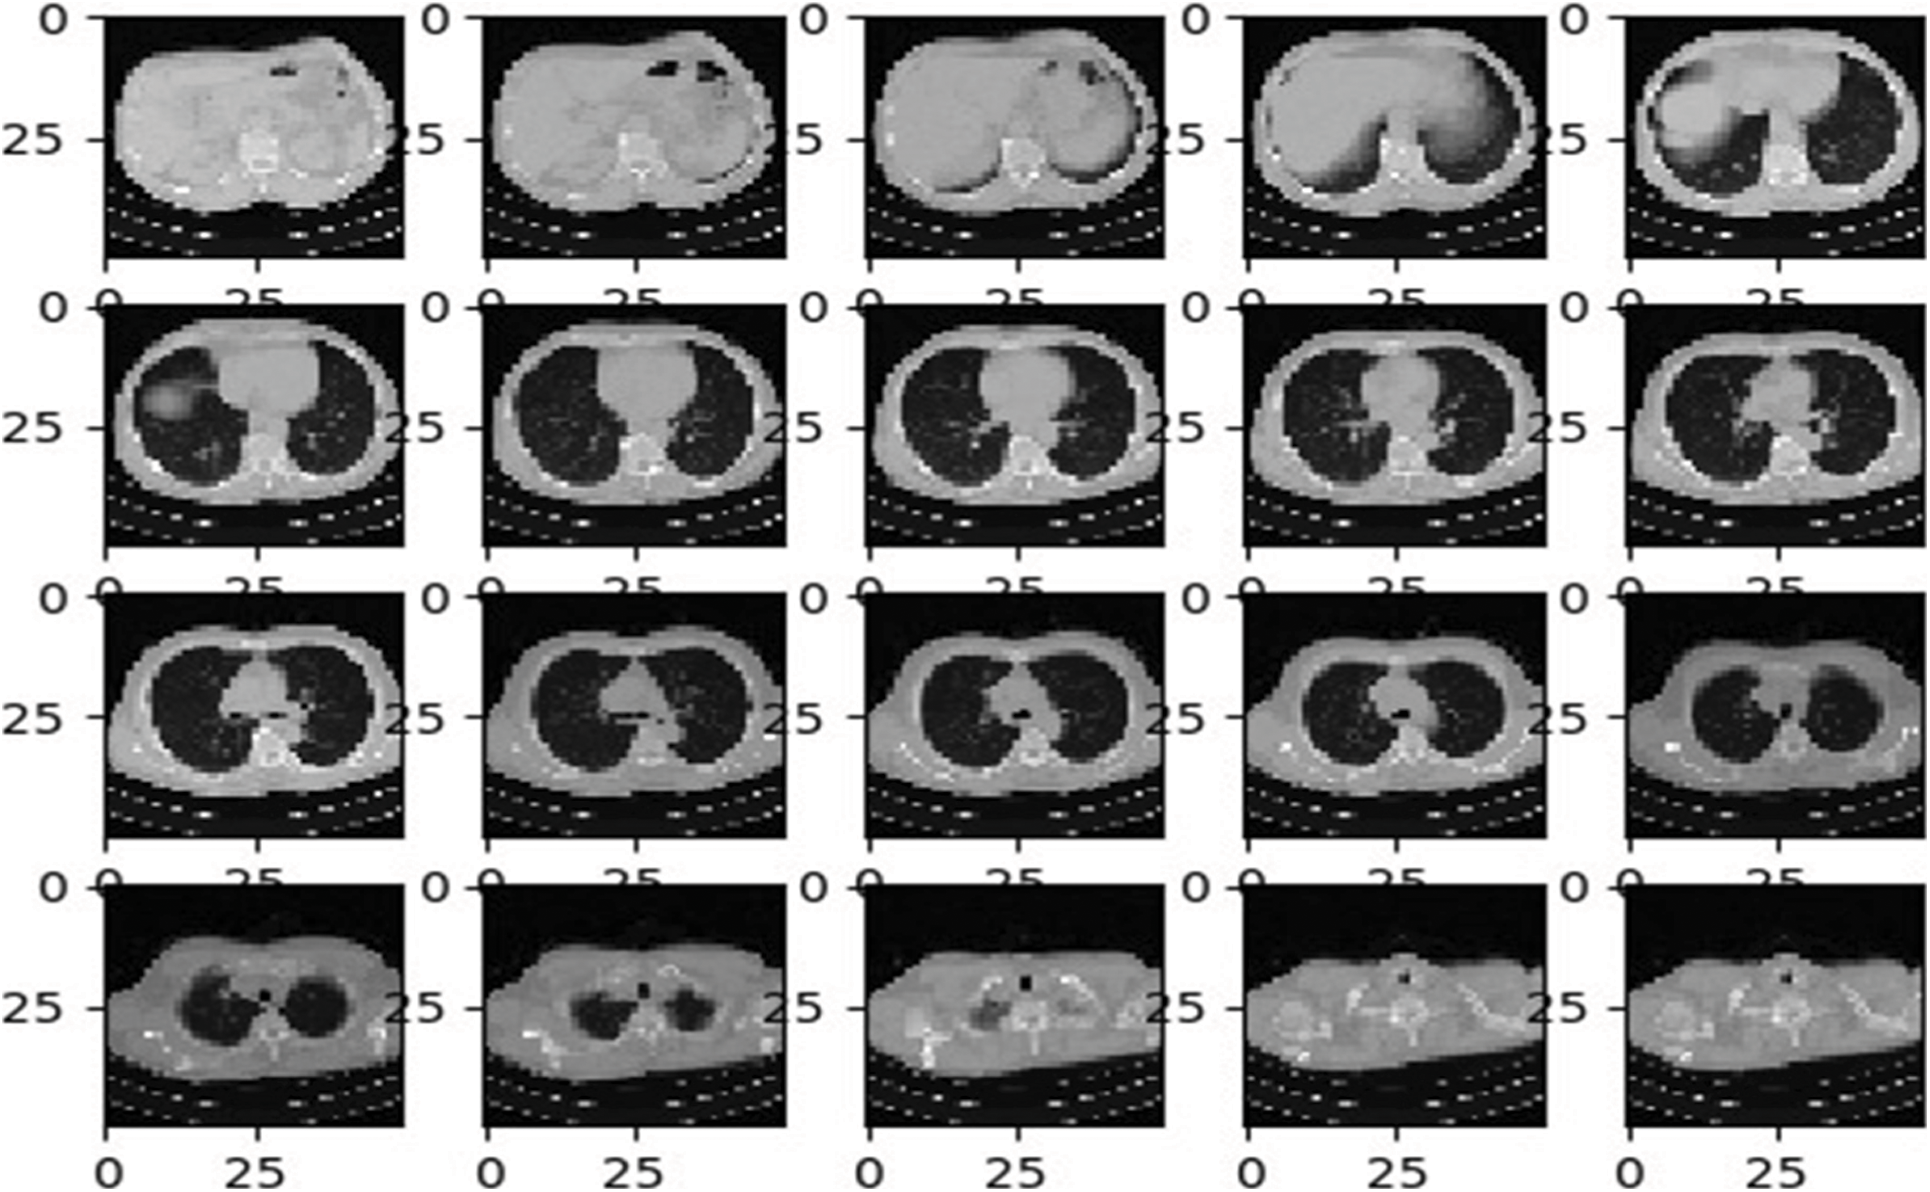

After preprocessing the input images, image augmentation process is used in the proposed architecture. Neural Networks leads to the overfitting problems where a limited quantity of labelled data is available. The most proficient and efficient method to tackle this problem is data augmentation. During the data augmentation phase, each image undergoes a series of transformation, producing the huge amount of newly corrected training image samples. As discussed in [31], affine transformation is employed for an efficient data augmentation. The affine transformation techniques such as translation, scaling and rotations are used. Mostly the training image samples obtained from the augmentation process have a correlation, this step is recommended to overcome the overfitting problems. Fig. 3 shows the different lung images obtained after applying the affine transformations.

Figure 3: Sample CT lung images after augmentation process